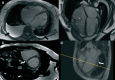

Case summary: We present the case of a 41-year-old female who was hospitalized for decompensated HF. Echocardiography revealed severe systolic dysfunction with a phenotype of dilated cardiomyopathy, accompanied by secondary moderate mitral regurgitation and severe tricuspid regurgitation (TR). To differentiate potential causes of HF, coronary angiography, cardiac magnetic resonance imaging (MRI), and endomyocardial biopsy were performed. Based on clinical findings, laboratory results, cardiac MRI, and endomyocardial biopsy data, a diagnosis of haemochromatosis was confirmed, and mutations in the TFR2 gene, responsible for haemochromatosis Type 3, were identified. The patient was treated in accordance with the latest European Society of Cardiology HF guidelines, and specific treatment for haemochromatosis, including therapeutic phlebotomy and iron chelation therapy, was initiated, resulting in a significant positive outcome.